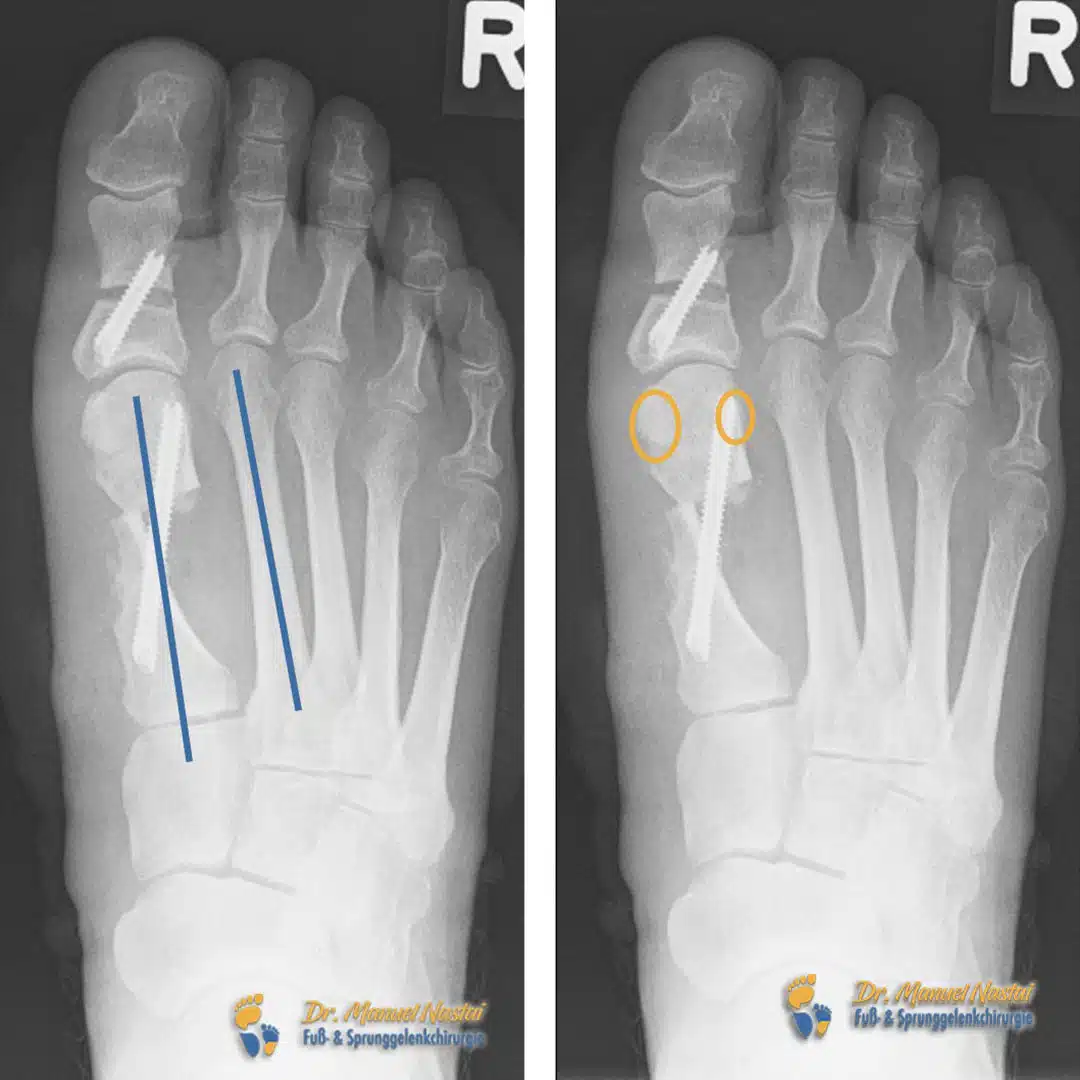

Röntgenbefund postoperativ

Nach minimalinvasiver Chevron-Korrektur mit Schraubenosteosynthese zeigt die belastete Aufnahme eine deutliche Achsenkorrektur. Der IMR1-Winkel (blau zu markieren) ist klar reduziert, die Längsachsen von M1 und M2 verlaufen wieder näherungsweise parallel – ein radiologisches Zeichen für die wiederhergestellte Ausrichtung des ersten Strahls.

Ebenso sind die Sesambeine (orange zu markieren) re-zentriert und liegen wieder plantar unter dem ersten Mittelfußkopf, beidseits der zentralen Führungsrinne. Diese Re-Zentrierung ist biomechanisch bedeutsam: Sie normalisiert die Hebelverhältnisse der Beugesehnen, verbessert die Lastverteilung im Großzehengrundgelenk und senkt das Rezidivrisiko.

Die Gelenkachsen zeigen sich harmonisiert, und der Großzehenstrahl steht gerade und konfliktfrei. Die sichtbaren Schrauben dokumentieren die stabile Fixation der Osteotomie in korrigierter Stellung.

- IMR1 in Blau: Längsachsen von M1 und M2 einzeichnen; der Winkel zwischen beiden entspricht dem IMR1.

- Sesambeine in Orange: Lage der medialen und lateralen Sesambeine unter dem M1-Kopf markieren (präoperativ lateralisiert, postoperativ zentriert).

- Achsenführung: Längsachsen zentral durch Köpfchen und Basis der beteiligten Mittelfußknochen legen, um die Korrektur anschaulich zu machen.

Postoperativ: IMR1 deutlich verkleinert, Sesambeine rezentriert, Achsen normalisiert – korrelierend mit einer entlasteten, funktionsfähigen Großzehe.